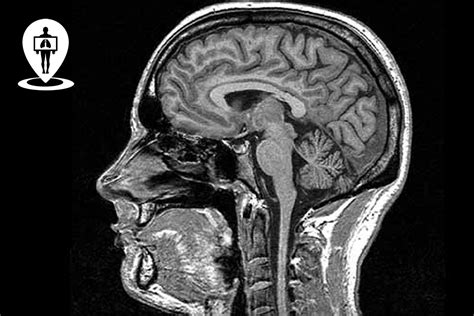

L'Importanza dell'Anatomia e della Funzione Cerebrale

Un requisito fondamentale per la comprensione delle problematiche neuropsicologiche è l'acquisizione di conoscenze relative all'anatomia e agli aspetti funzionali del sistema nervoso centrale e periferico. Lo studente deve acquisire competenze concernenti l'organizzazione neuroanatomica e funzionale del sistema nervoso, comprendendo i potenziali e i limiti delle tecniche di acquisizione dei segnali cerebrali e delle immagini anatomiche. Questi strumenti sono indispensabili per comprendere l'architettura del sistema nervoso e i moduli funzionali che lo compongono.

L'acquisizione di conoscenze sui metodi di neuroimmagine utilizzati nelle neuroscienze cognitive, sul loro grado di evidenza causale e sul contributo di ciascuna metodica alla comprensione del rapporto mente-cervello è un obiettivo formativo chiave. Questo include lo sviluppo della capacità di analisi critica degli argomenti trattati, individuando i punti di forza e i limiti delle diverse metodiche. L'interpretazione dei risultati presentati in articoli scientifici peer-review, mediante le più moderne tecniche di visualizzazione anatomica e in vivo del cervello, è un'altra competenza essenziale.

Individuazione e Analisi dei Circuiti Neurali

La capacità di individuare ed esaminare i circuiti che compongono i principali sistemi sensoriali e motori, attraverso le più moderne tecniche di visualizzazione anatomica e in vivo del cervello, permette una comprensione approfondita delle basi neurali delle funzioni cognitive. Questa competenza è cruciale per interpretare i risultati di ricerche scientifiche innovative e valutarne il potenziale impatto sull'organizzazione anatomica e funzionale del cervello e sulle metodiche di riabilitazione neuropsicologica.